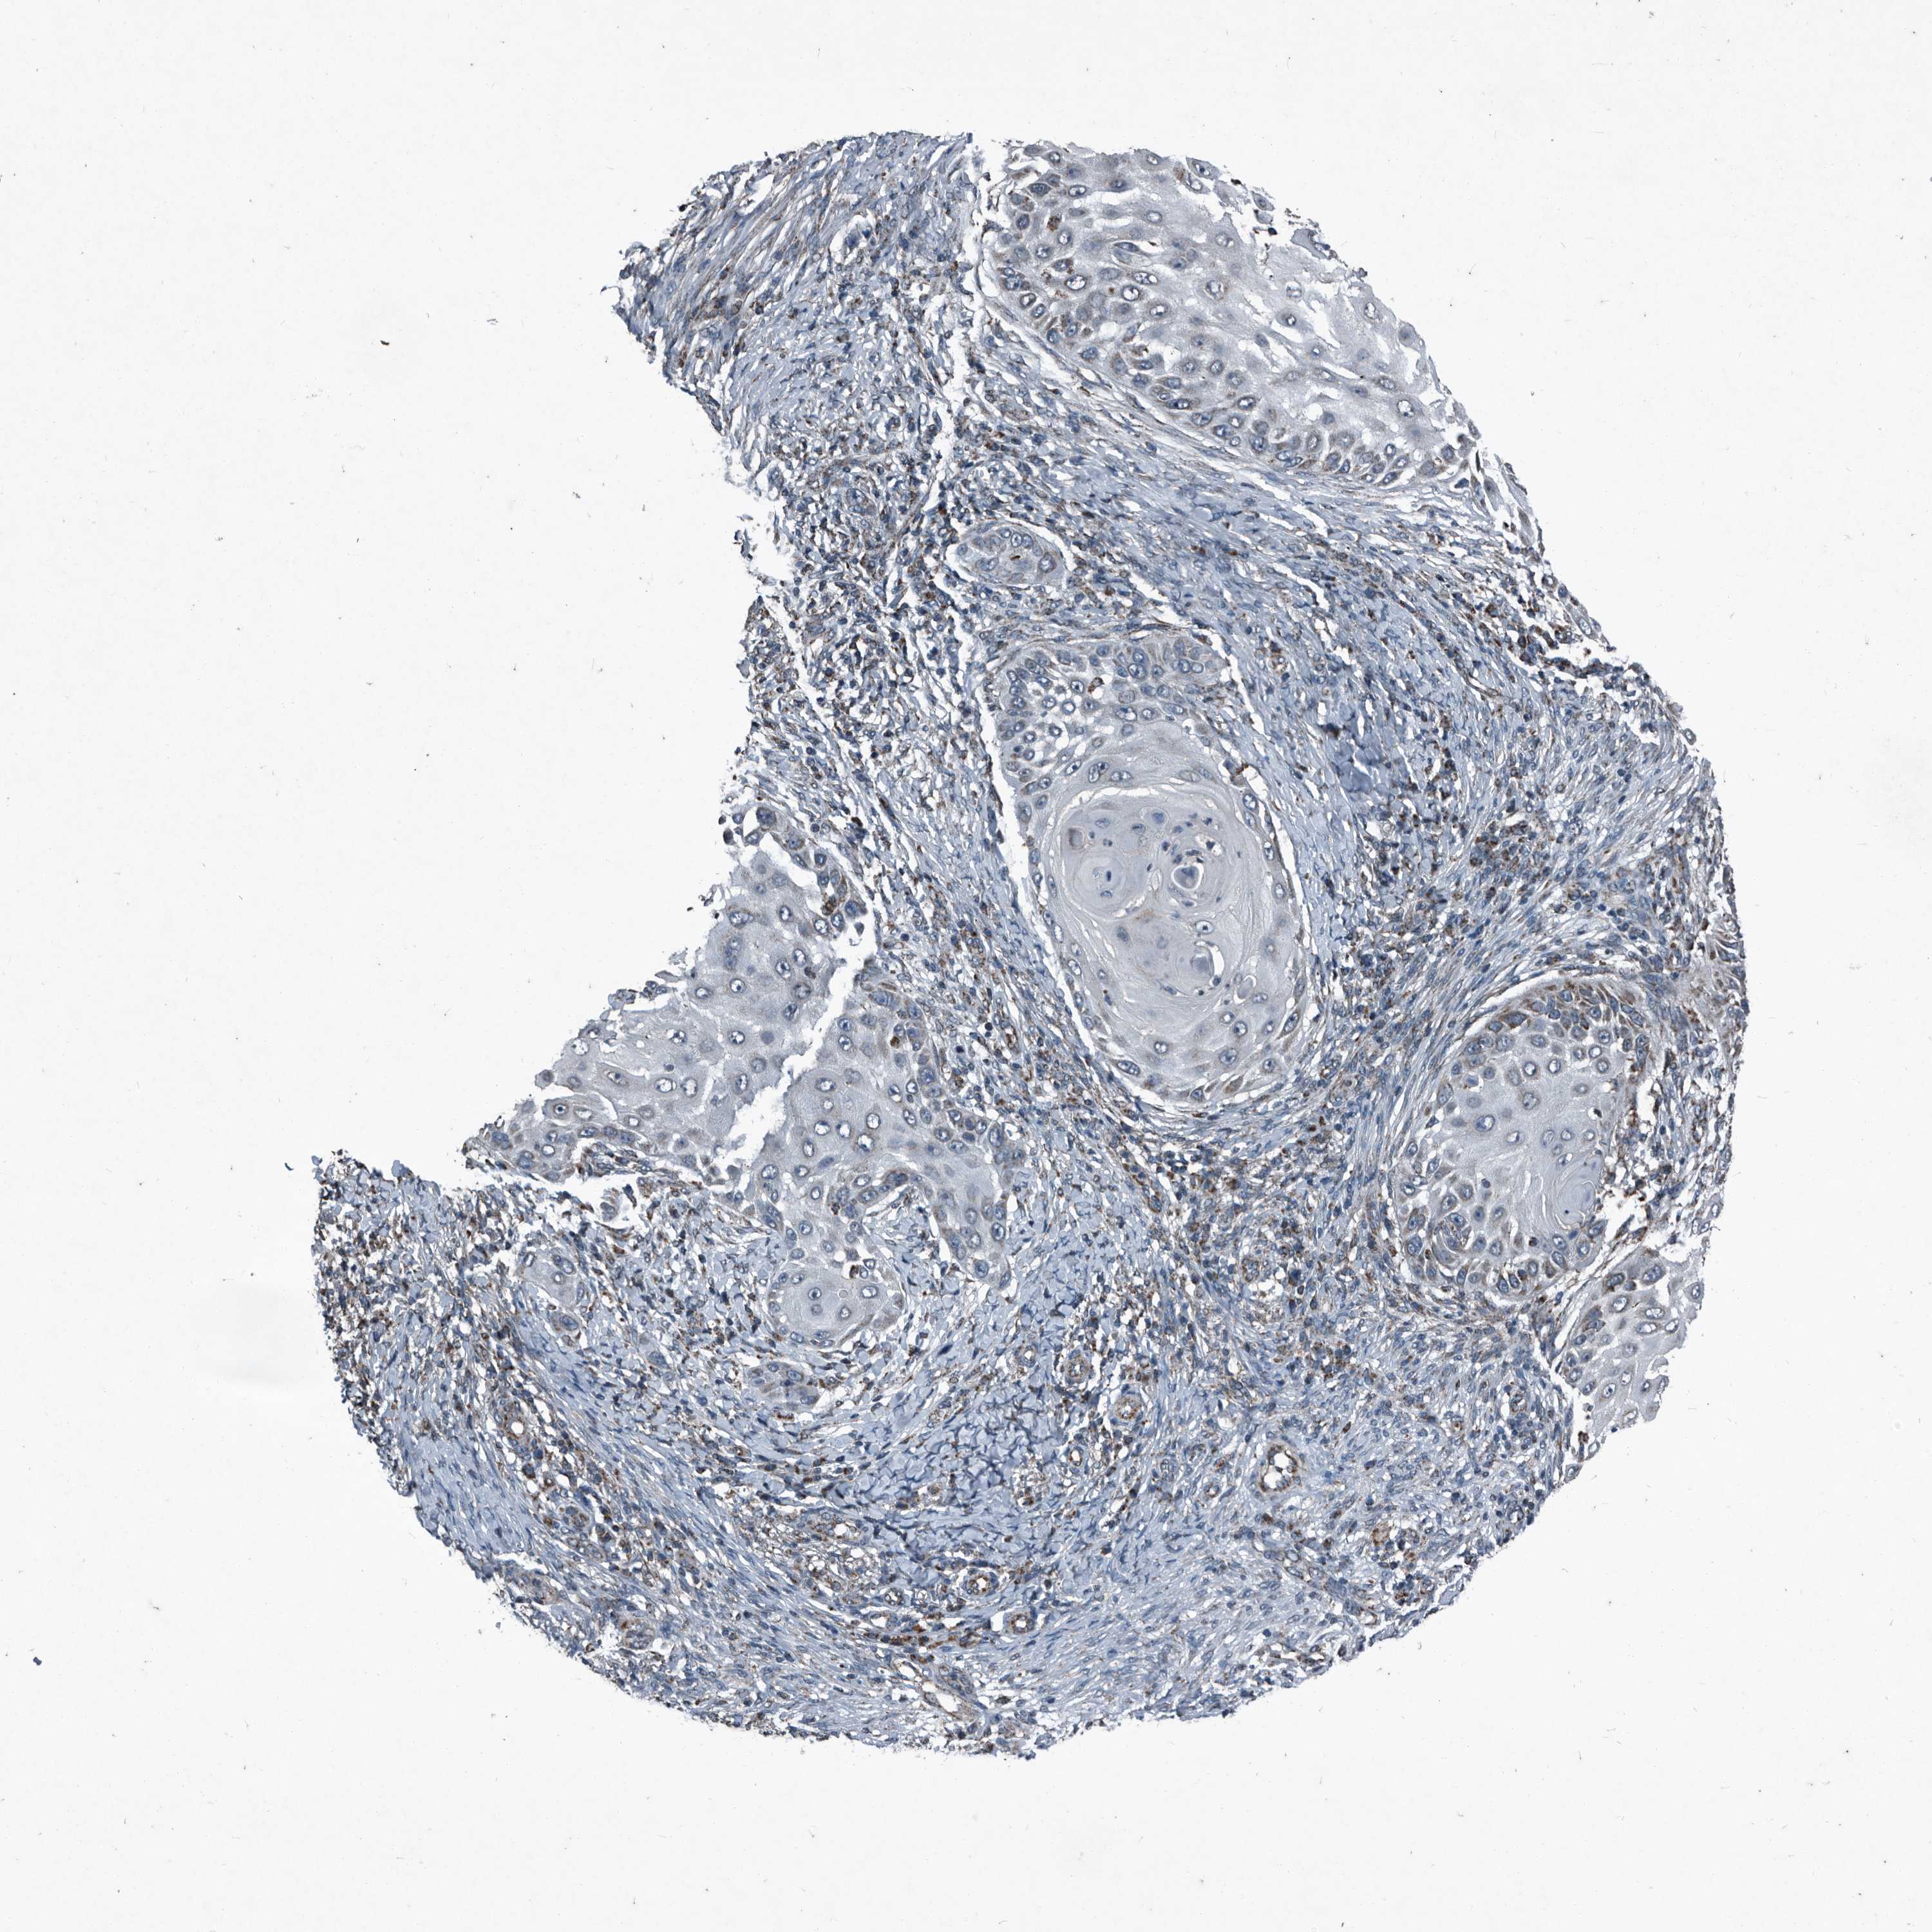

SKIN CANCER - Protein expressioni

A mouse-over function shows sample information and annotation data. Click on an image to view it in a full screen mode. Samples can be filtered based on level of antibody staining by selecting one or several of the following categories: high, medium, low and not detected. The assay and annotation is described here.

Antibody stainingi

Antibody staining in the annotated cell types in the current human tissue is reported as not detected, low, medium, or high, based on conventional immunohistochemistry profiling in selected tissues. This score is based on the combination of the staining intensity and fraction of stained cells.

Each image is clickable and will lead to virtual microscopy that enables deeper exploration of all samples and also displays staining intensity scores, fraction scores and subcellular localization as well as patient and tissue information for each sample.

Antibody HPA045174

Antibody CAB032821

Staining

High

Medium

Low

Not detected

Intensity

Strong

Moderate

Weak

Negative

Quantity

>75%

75%-25%

<25%

None

Location

Nuclear

Cytoplasmic/membranous

Cytoplasmic/membranous,nuclear

Basal cell carcinoma

BCC, high aggressive

Squamous cell carcinoma, NOS

Squamous cell carcinoma, metastatic, NOS